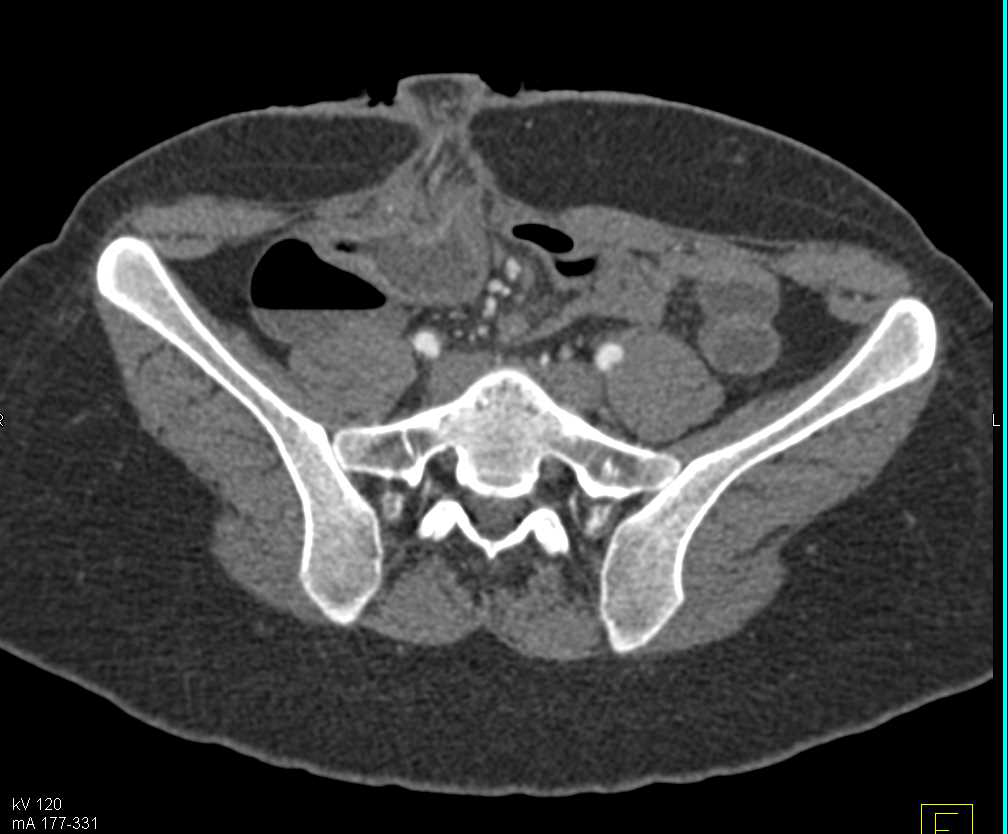

Omental Infarct Left Upper Quadrant Following Distal Pancreatectomy and Splenectomy